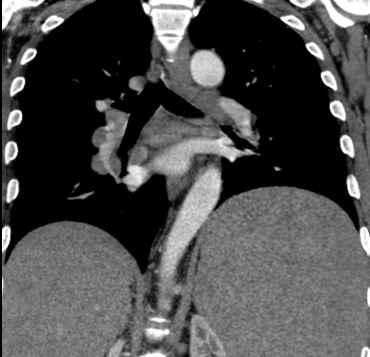

Lymphoma  coronal CT